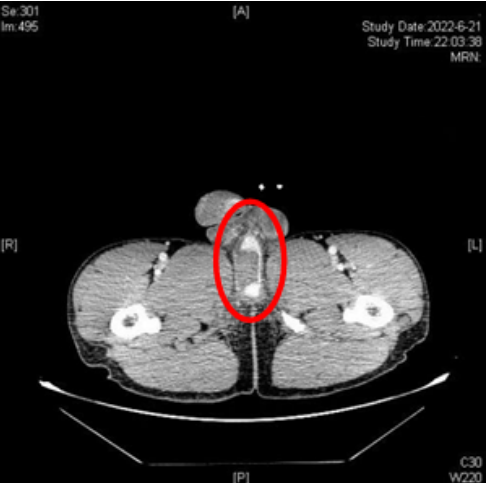

无独有偶,来自慈利的刘强(化名)一直在长沙工地做事,近日在拆高处脚手架时不慎从高处摔落,骑跨于钢杆上,当时出现会阴部血肿、阴囊血肿、尿道口滴血、排尿不出。工友立即将其送往香港马会app,急诊CT发现刘强阴茎海绵体撕裂、尿道海绵体断裂、会阴软组织挫伤、血肿、左侧第11-12肋骨骨折,泌尿外科会诊后随即行急诊手术,将断裂尿道进行修补。

CT示患者阴茎海绵体部分撕裂,尿道海绵体断裂、造影剂外漏,海绵体周围软组织挫伤